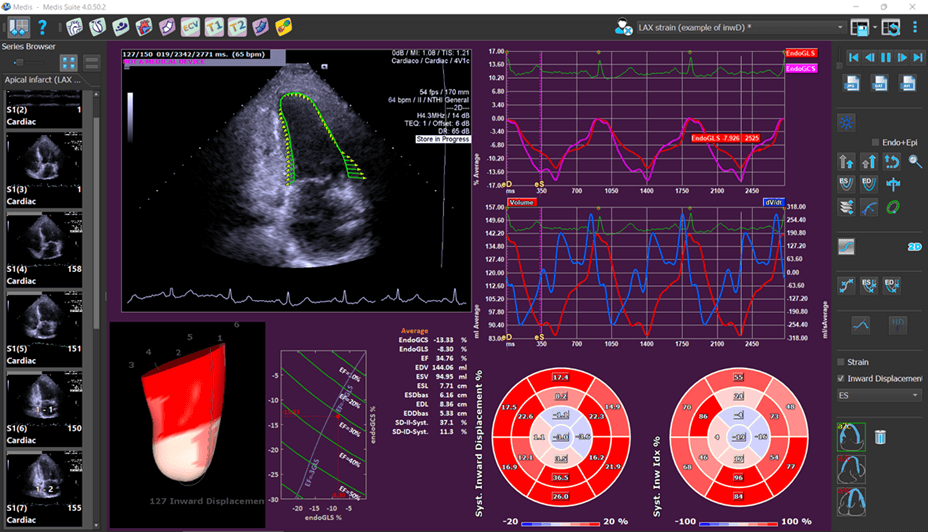

Medis Suite Ultrasound is the latest addition to the Medis Suite portfolio for cardiovascular imaging. Based on 20 years of developments and innovations, we bring you the latest image post-processing tools in advanced cardiac deformation analysis for echo. Medis Suite Cardiac Ultrasound (Echocardiography) is currently available for research use. Medis Suite Ultrasound is a continuation of over 20 years of innovative algorithms and ground-breaking work in Echocardiography software by AMID. AMID was acquired by Medis in 2020.

- Considered by many the gold standard vendor independent software for advanced cardiac deformation analysis, providing deeper insight into heart function

- Allows the quantitative evaluation of the Left Ventricle, Right Ventricle and the Left Atrium OEM solution. See the applications below for further details